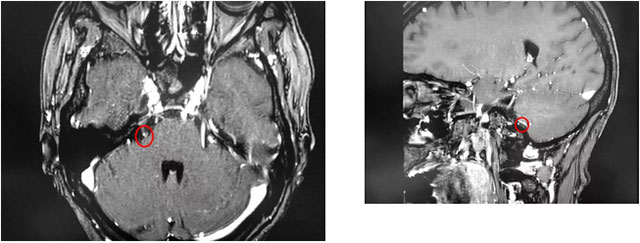

▲ 患者右側(cè)三叉神經(jīng)與周圍小血管關(guān)系密切

最近,金女士慕名來到上海藍十字腦科醫(yī)院尋求進一步治療。沈建康教授和醫(yī)院神經(jīng)外科6B病區(qū)潘仁龍主任團隊結(jié)合患者病史和影像學(xué)分析,判斷患者右側(cè)三叉神經(jīng)與周圍小血管關(guān)系密切,經(jīng)開展嚴謹?shù)脑u估討論并取得家屬同意后,沈建康教授為金女士開展了微血管減壓手術(shù)。